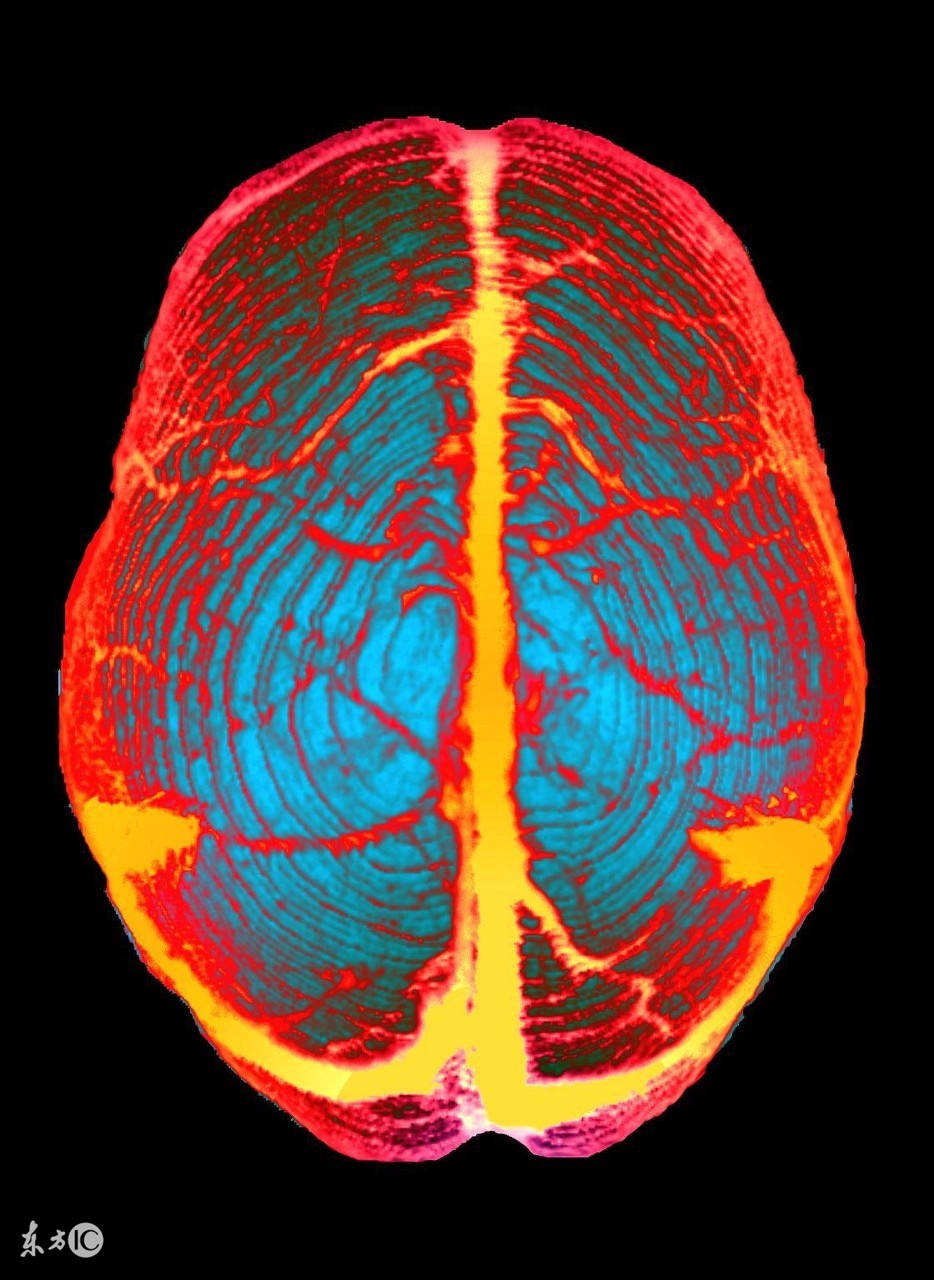

CT 作为神经系统最常用的检查手段,在静脉窦血栓的诊断中同样发挥着重要作用。尤其是近年来多排、高分辨率 CT 的应用, CVST 早期诊断率明显提高。怀疑后颅窝静脉窦血栓形成时,为了减少扫描伪影,需行以静脉窦为中心的连续薄层扫描,易于发现位于静脉窦(横窦、乙状窦或直窦)走行部位条带状高密度静脉窦血栓影,以免误诊为蛛网膜下腔出血,误导治疗。静脉窦血栓患者 CT 平扫的 直接征象与静脉窦位置一致的高密度条带征, 诊断正确率与 CT 扫描技术相关 。 单纯皮质静脉血栓患者 CT 扫描直接征象为位于脑表面蛛网膜下腔的 条索状或三角形密度增高影。CT平扫间接征象包括:弥漫的脑组织肿胀(脑回肿胀、脑沟变浅和脑室受压)、静脉性梗死和特征性的脑出血(位于皮质和皮质下脑组织之间、常双侧对称)。增强 CT呈现典型的δ征(中间低密度,周边高密度)。 然而, CVST 患者头颅 CT 扫描 20% ~ 30% 正常,表现为单纯颅内压增高的患者高达 50% 头颅 CT 无异常发现。 CTV 具有良好的空间分辨力,且无血流相关伪影,具有较高的敏感度和特异度,可同时显示静脉窦闭塞和窦内血栓。 CT 结合 CTV 对静脉窦血栓做出确定诊断,可作为 CVST 疑似患者的首选影像学方法,其敏感度可达 75% ~ 100% ,特异度可达 81% ~ 100% 。另外, CT 与 CTV 的联合应用,可以观察脑动、静脉病变,也可以观察脑组织结构改变。但增强扫描所用造影剂过敏和 X 线辐射限制了其反复用于随访检查。

二、头颅 MRI/MR静脉成像(MRV)

可直接显示颅内静脉和静脉窦血栓,以及继发于血栓形成的各种脑实质损害,较 CT 更为敏感和准确,但血栓表现随发病时间不同而变化,其中又以亚急性期的血栓高信号对 CVST 诊断较为可靠。磁敏感加权成像( SWI )或 T2* 加权梯度回波( T2*GE ) 等序列较 MR 常规序列对显示脑内出血更加敏感,对诊断 CVST 比常规系列成像具有更高的敏感度和特异度。头颅 MRV 可发现相应的静脉窦主干闭塞,皮质静脉显影不良,侧裂静脉等侧支静脉扩张,板障静脉和头皮静脉显像等征象。在大多数情况下, MRI/MRV 已可对 CVST 进行准确诊断,且所用增强剂更安全又没有 X 线辐射,被认为是诊断和随访 CVST 的最佳手段,但局部单纯的皮质静脉显示能力较弱,以及不能判断静脉血流方向是其主要不足之处。在 MRV 发现一侧静脉(窦)血流缺失时,并不能判断是由于血栓或是先天闭塞所造成。有研究者建议,若 CT 上双侧下颌切迹对称则支持 CVST 的诊断。 MRV 包括时间飞跃 MRV ( TOF MRV )、相位对比血管成像( PCA )和对比增强 MRV ( CE MRV ) 3 种成像方法,与 TOF MRV 和 PCA 相比, CE MRV 由于消除了血管内湍流,使颅内静脉和静脉窦显示更为清晰,如同时结合数字减影 MRA ( DSMRA )和最大密度投影( MIP )重建等技术,可多角度显示静脉血管的三维影像,因此, CE MRV 可作为 MRV 的首选成像方法。